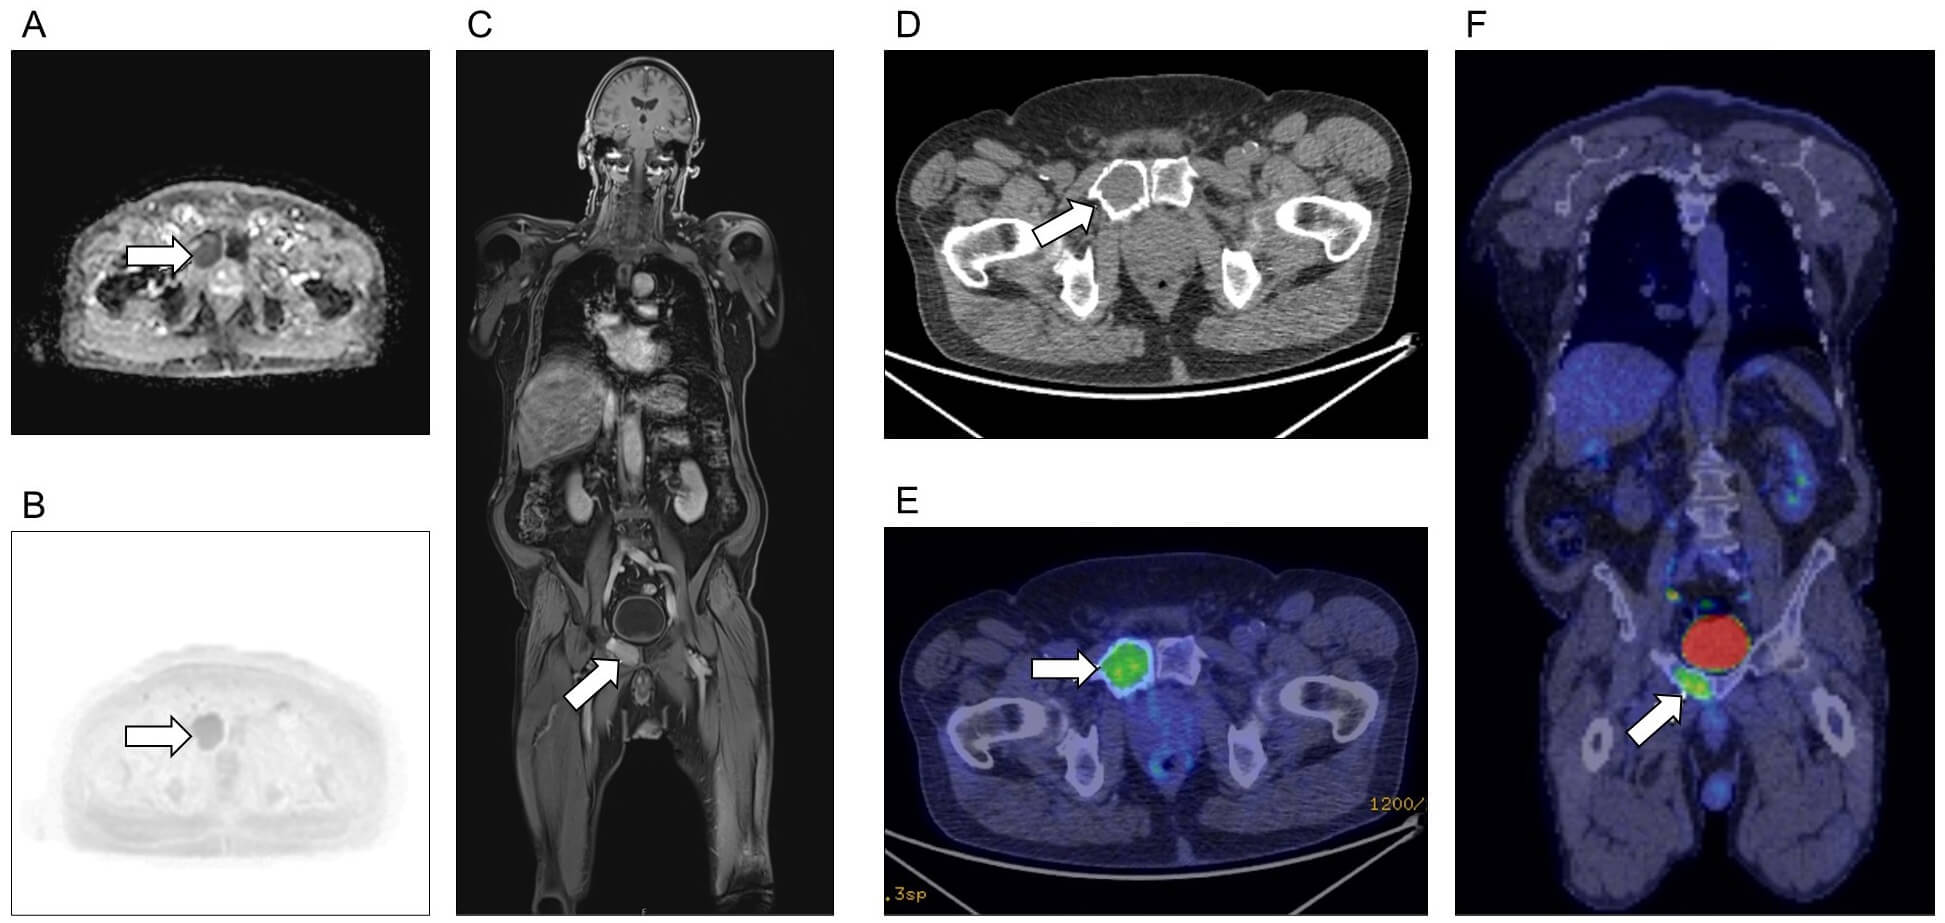

Fig. 4.

Plasmacytoma affecting bone. Solitary plasmacytoma (arrows) of the right pubic bone, as seen on (A–C) MRI and (D–F) FGD-PET/CT. (A) Apparent diffusion coefficient axial image. (B) DWI axial image. (C) T1 post-contrast coronal image. (D) CT only axial image. (E) Fused CT and FDG-PET axial image. (F) Fused coronal image. Imaging of both modalities identified no additional sites of disease.

International guidelines recommend WB-MRI to assess patients with newly diagnosed bone plasmacytoma, and FDG-PET/CT for extramedullary plasmacytoma [36], although there are data showing WB-MRI has higher sensitivity also for extramedullary disease [50].